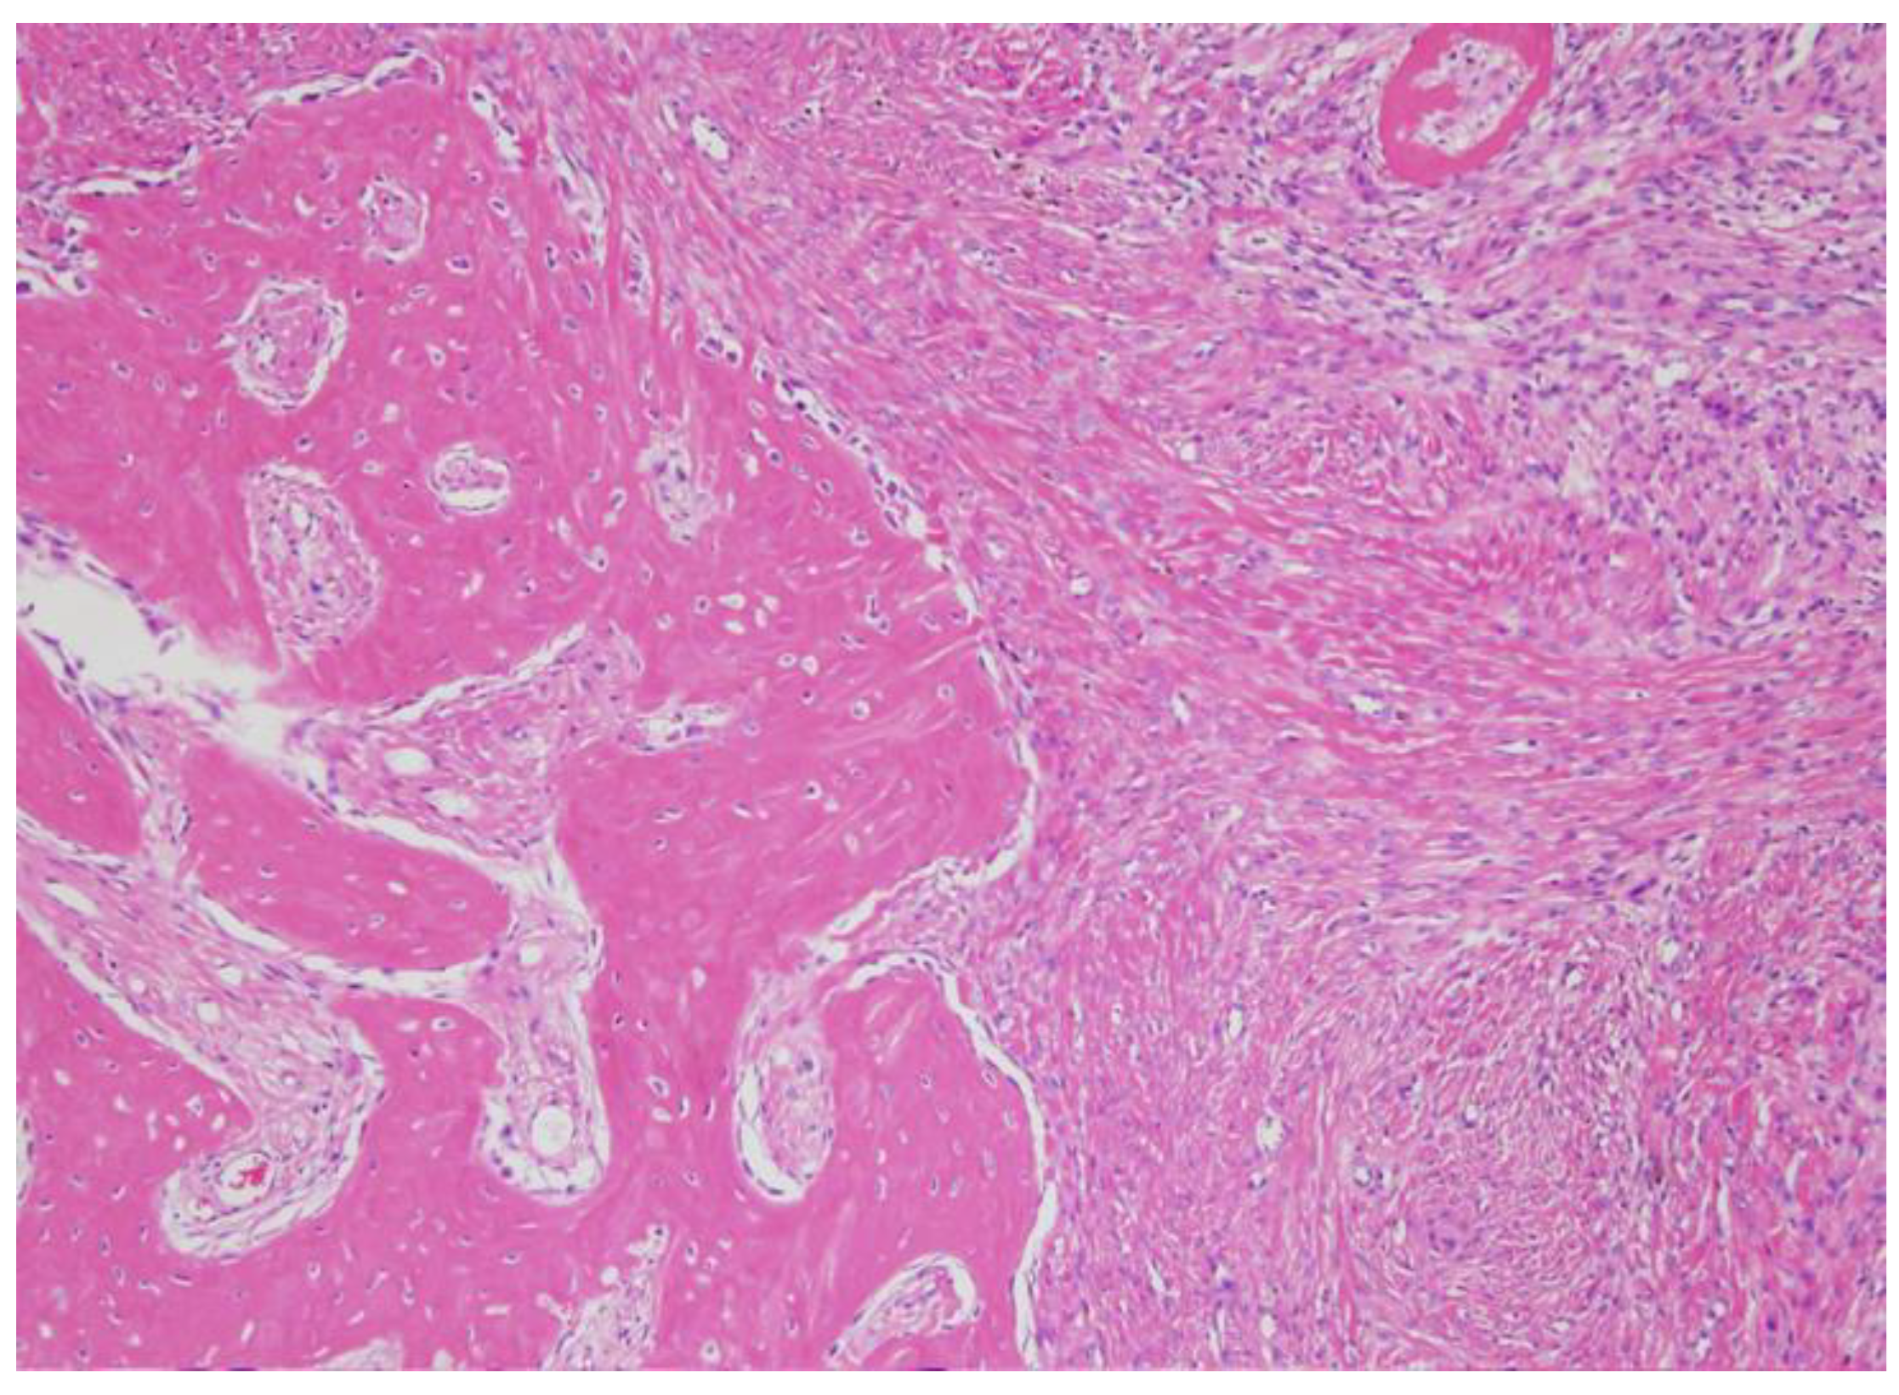

2.3. Diagnosis and Management

3. Discussion